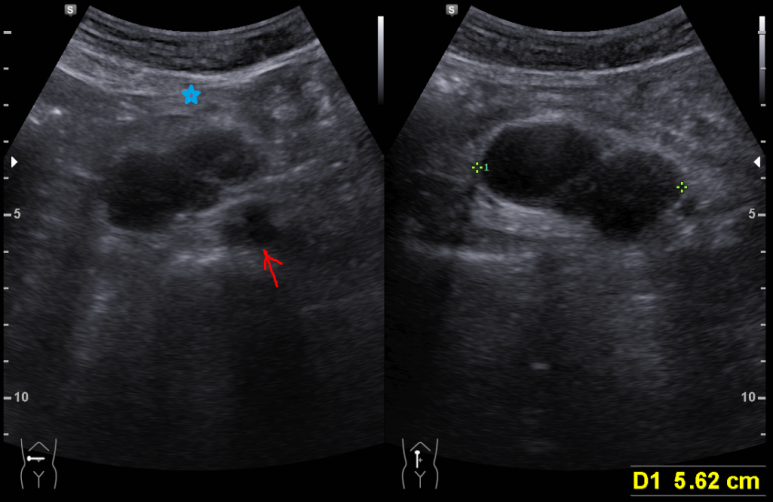

60대 여자

무증상

배꼽 직상부

화살표는 대동맥

5.6 cm 낭성 종양 직 상부로 상장간막 동맥, 정맥이 위치하고 있다. (파란 별 아래 위치)

anterior pararenal space에 위치하는 것으로 생각된다.

진단; Cystic mass

ddx; lymphangioma, cystic change of neurogenic tumor, cystic lymphadenopathy